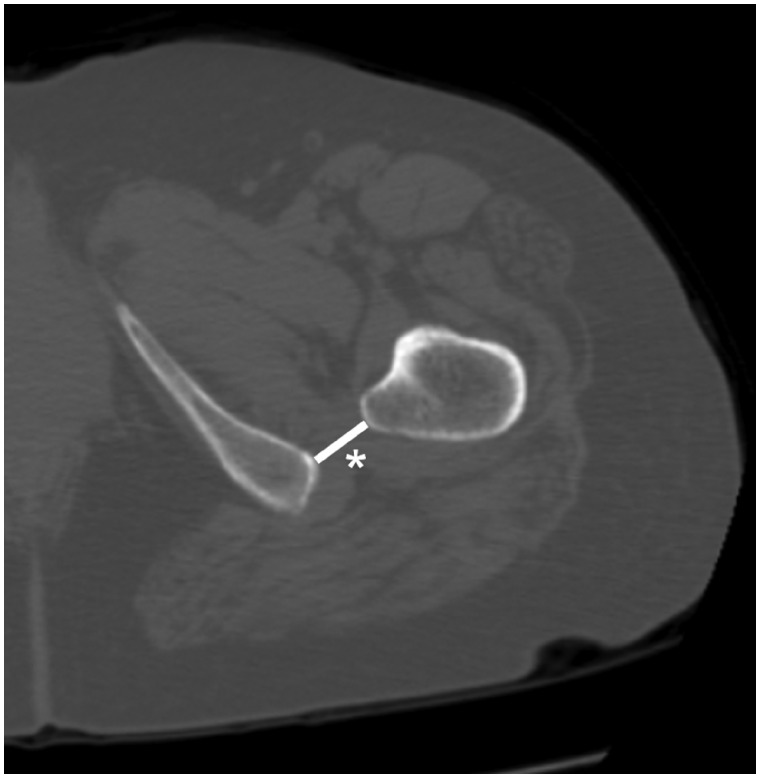

We retrospectively examined 89 consecutive Japanese individuals (46 male and 43 female subjects) who met the above criteria. Both hips were analysed in each patient. IFS was measured as the shortest distance (on an axial image) between the lateral ischial bone surface and the medial bone surface of the lesser trochanter (Fig. 2). We established the mean IFS value in this cohort and then compared it with that reported by Hujazi et al. [7], whose measurements were of a similar cohort using the same examination protocol.

Fig. 2.

Method for measuring ischiofemoral space (IFS). The IFS (*) was measured as the shortest distance between the lateral bone surface of the ischium and the medial bone surface of the lesser trochanter.